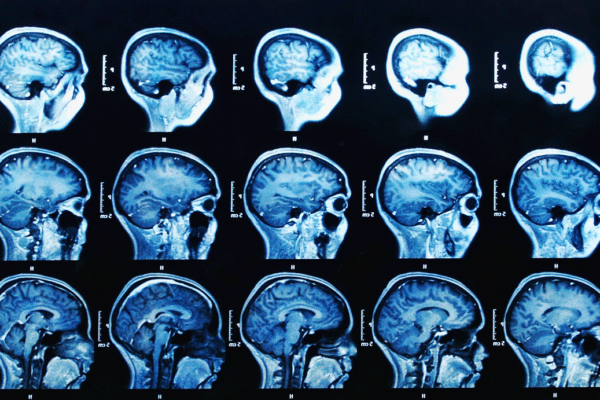

על פי דיווח החברה, כבר בשלב הראשוני של הניסוי הקליני התקבלו תוצאות חיוביות שבאו לידי ביטוי בהפחתה של כמויות העמילואיד (חלבון בלתי מסיס), המצטבר במוח אצל

חולי אלצהיימר. כמו כן, נרשמה האטה משמעותית בירידה הקוגניטיבית האופיינית לחולים במחלה בשלב החומרה הבינוני שלה.